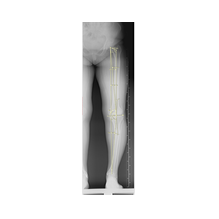

Ameliyat öncesi deformitenin iyi analiz edilmesi, planlamanın ona göre yapılması gerekir. Deformite düzeltilmesi esnasında eğer kısalık var ise sıra ile iki problemin de aynı anda düzeltilmesi mümkündür.

Bu ameliyat öncesi bir deformite analizi yapılıp hangi kemikte, normalden ne kadar sapma olduğu tespit edilir. Daha sonra bu kemiğe yine ostetomi yapılarak bu anormal sapma düzeltilir.  Bu düzeltme plak-vida veya intramedüller çivi ile akut olarak düzeltilebileceği gibi bilgisayar destekli sirküler eksternal fiksatör ile tedrici olarak ta yapılabilir. Hangi yöntemin hangi hasta için uygun olacağına hasta özelinde karar veriyoruz, ne tür cerrahi tedavi olması gerektiğini danışabilirsiniz.

Görüntüleri büyütmek için üzerine tıklayınız.